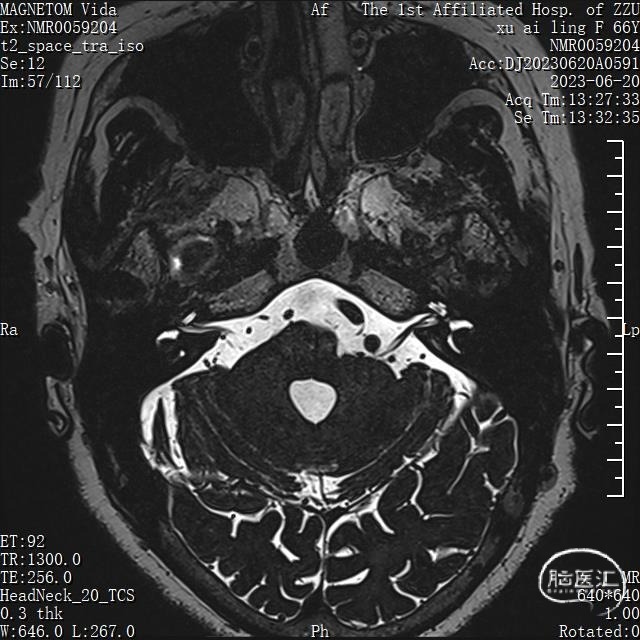

术前MRI:可见面神经REZ区有血管影,但是其信号与动脉信号有区别。同时因后颅窝解剖结构变异,乙状窦位置可能影响CPA区暴露

术前诊断:左侧面肌痉挛,考虑责任血管为:小脑前下动脉或脑干静脉

现病史:4月前无明显诱因出现左侧眼睑部间断抽搐,口服药物无好转,抽搐逐渐发展至左侧面颊部左侧嘴角,在情绪紧张及与人交谈时明显加重,遂来我院门诊就诊,行面神经电生理检查提示:侧方扩散反应(LSR)阳性,当时未住院治疗,1周来症状明显加重,抽搐频繁,再次来我院检查行头部MRI-3D-TOF-MRA未见明显动脉血管压迫,左侧CPA无占位病变。